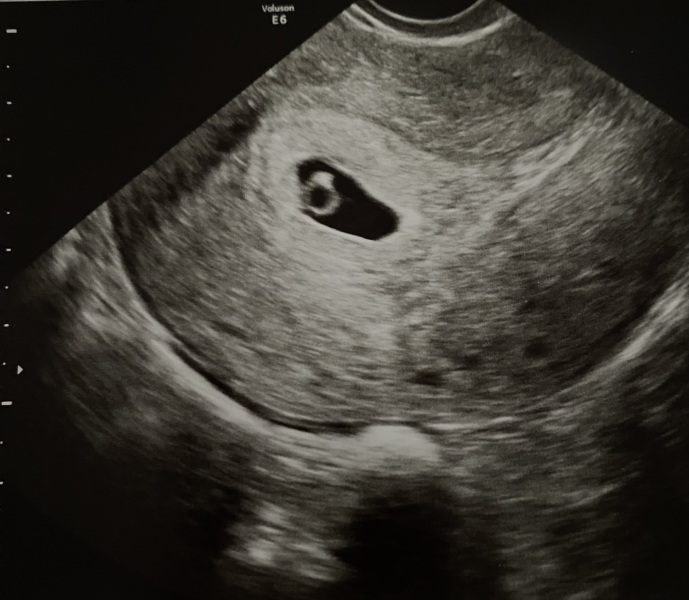

We had a viability scan last weekend at 6 weeks 1 day as I just needed a little assurance that everything was okay. They said I was measuring about 5 weeks but they weren’t worried. Left feeling quite panicked as I lost a baby last summer as they were measuring a week behind and then their heart stopped beating. It’s all a bit sensitive as both babies have been through IVF so they are beyond wanted!

Has anybody gone through baby measuring behind? Trying to remind myself that they’re so small right now that an accurate measurement is so hard!

@Priceslice looks more like maybe the end of week 5 so you could only be a few days earlier. Could be late implantation or even late ovulation. Being off by a couple days is normal.

EDD of 15th October. I had some bleeding two weeks ago, then an early scan at what was 6 weeks by LMP where they could only see the gestational sac. The sonographer said ‘we’d normally like to see the yolk sac by 6 weeks’ so after an anxiety filled week, I had another scan and all is there where it’s supposed to be with a heartbeat ❤️ I was measuring 6w1d and I knew I had ovulated late so it makes sense.

I had my scan this morning and I may need to switch threads... I'm 8+3 weeks! I think that gives me a late September/early October due date!

Heart beat and looking good!